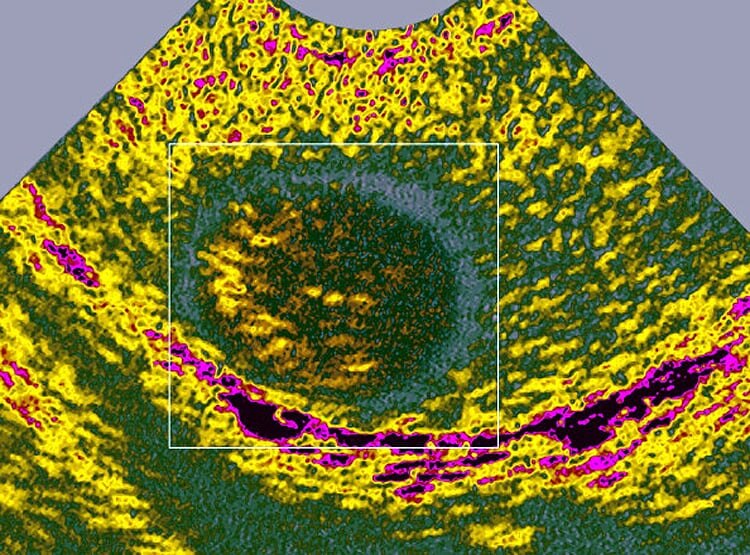

दोनों डॉक्टरों ने बताया कि इस महिला को टेस्टीक्यूलर कैंसर (Testicular Cancer) है. जो पुरुषों को होता है. ये महिला जिस दुर्लभ स्थिति में है, वह 22 हजार लोगों में से किसी एक को होता है.(प्रतीकात्मक फोटोः गेटी)

इस महिला में पुरुषों के अंडकोश हैं. जो उसके शरीर के अंदर हैं. उसमें कैंसर हो गया है. टेस्टीक्यूल कैंसर को सेमिनोमा (Seminoma) भी कहते हैं. इस महिला के पास आम महिलाओं की तरह सभी जननांग हैं, लेकिन वो गर्भवती नहीं हो सकती. (प्रतीकात्मक फोटोः गेटी)

डॉक्टरों ने महिला के पुरुष होने की पुष्टि करने के लिए कैरियोटाइपिंग टेस्ट कराया. जिसमें शख्स के क्रोमोसोम्स का अध्ययन किया जाता है. उसके क्रोमोसोम्स XY हैं, जो कि पुरुषों के होते हैं. जबकि, महिलाओं के XX होते हैं. (प्रतीकात्मक फोटोः गेटी)